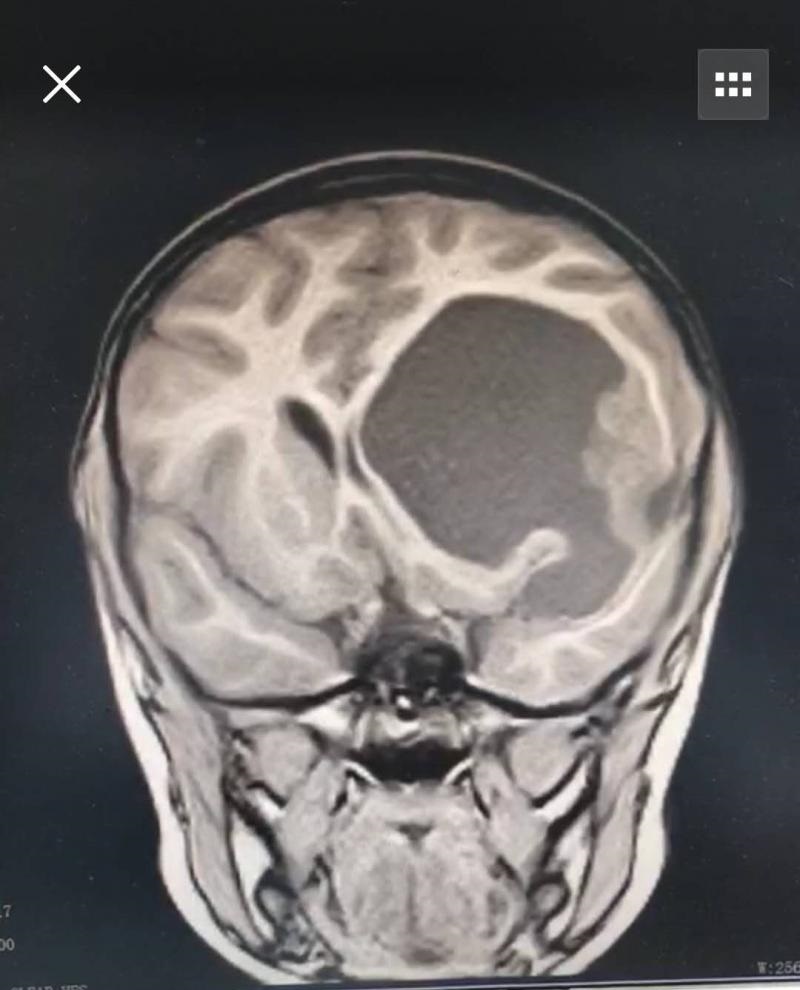

据小宝的主刀医生高峰博士介绍,小宝患的是间变型室管膜,属于脑胶质细胞瘤的一种。这种瘤属于中枢神经系统肿瘤,种类很多,有些是良性,但大部分是恶性,胶质瘤患者以尤男性比较多见。

术前影像